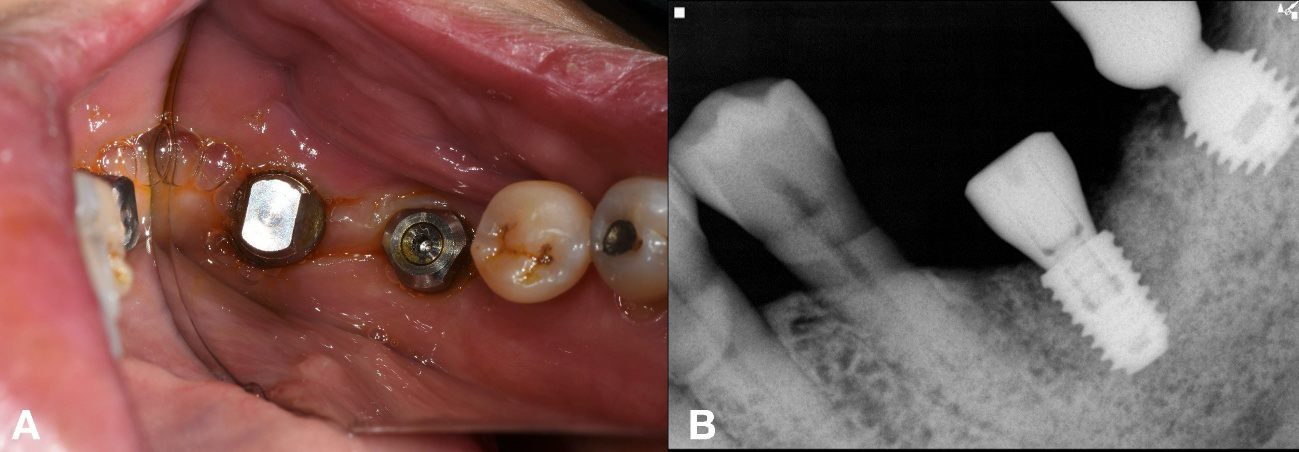

Approximately 3 months after implant placement of #36 implant, prosthetic rehabilitation was initiated. A custom abutment was fabricated for #36, and a new abutment was delivered for the salvaged, preexisting fixture of implant #37 (Figs. 4 and 5).

A 69-year-old male presented with discomfort in the left mandibular molar region. Tooth #36 was deemed hopeless and subsequently extracted, whereas the adjacent #35 implant exhibited a fractured crown on an existing undocumented fixture.6, 7 Two months after a GBR with a FDBA at site #36, a new implant (TSIII, 4.5 mm diameter and 8.5 mm length; Osstem Implant) was placed with an initial torque of 35 Ncm. A healing abutment (5 mm diameter, and 7 mm height) was simultaneously placed. As the implant at site #35 remained undocumented, the KAOMI team again was consulted. The fixture was identified as SS-2 (SS-2; Osstem Implant) (Fig. 7).

An appropriate stock abutment for fixture (#35) was procured, enabling reuse of the existing implant for patient comfort and reduced surgical morbidity. The restoration was completed based on the information provided by the implant finder service (Fig. 8A and 8B).